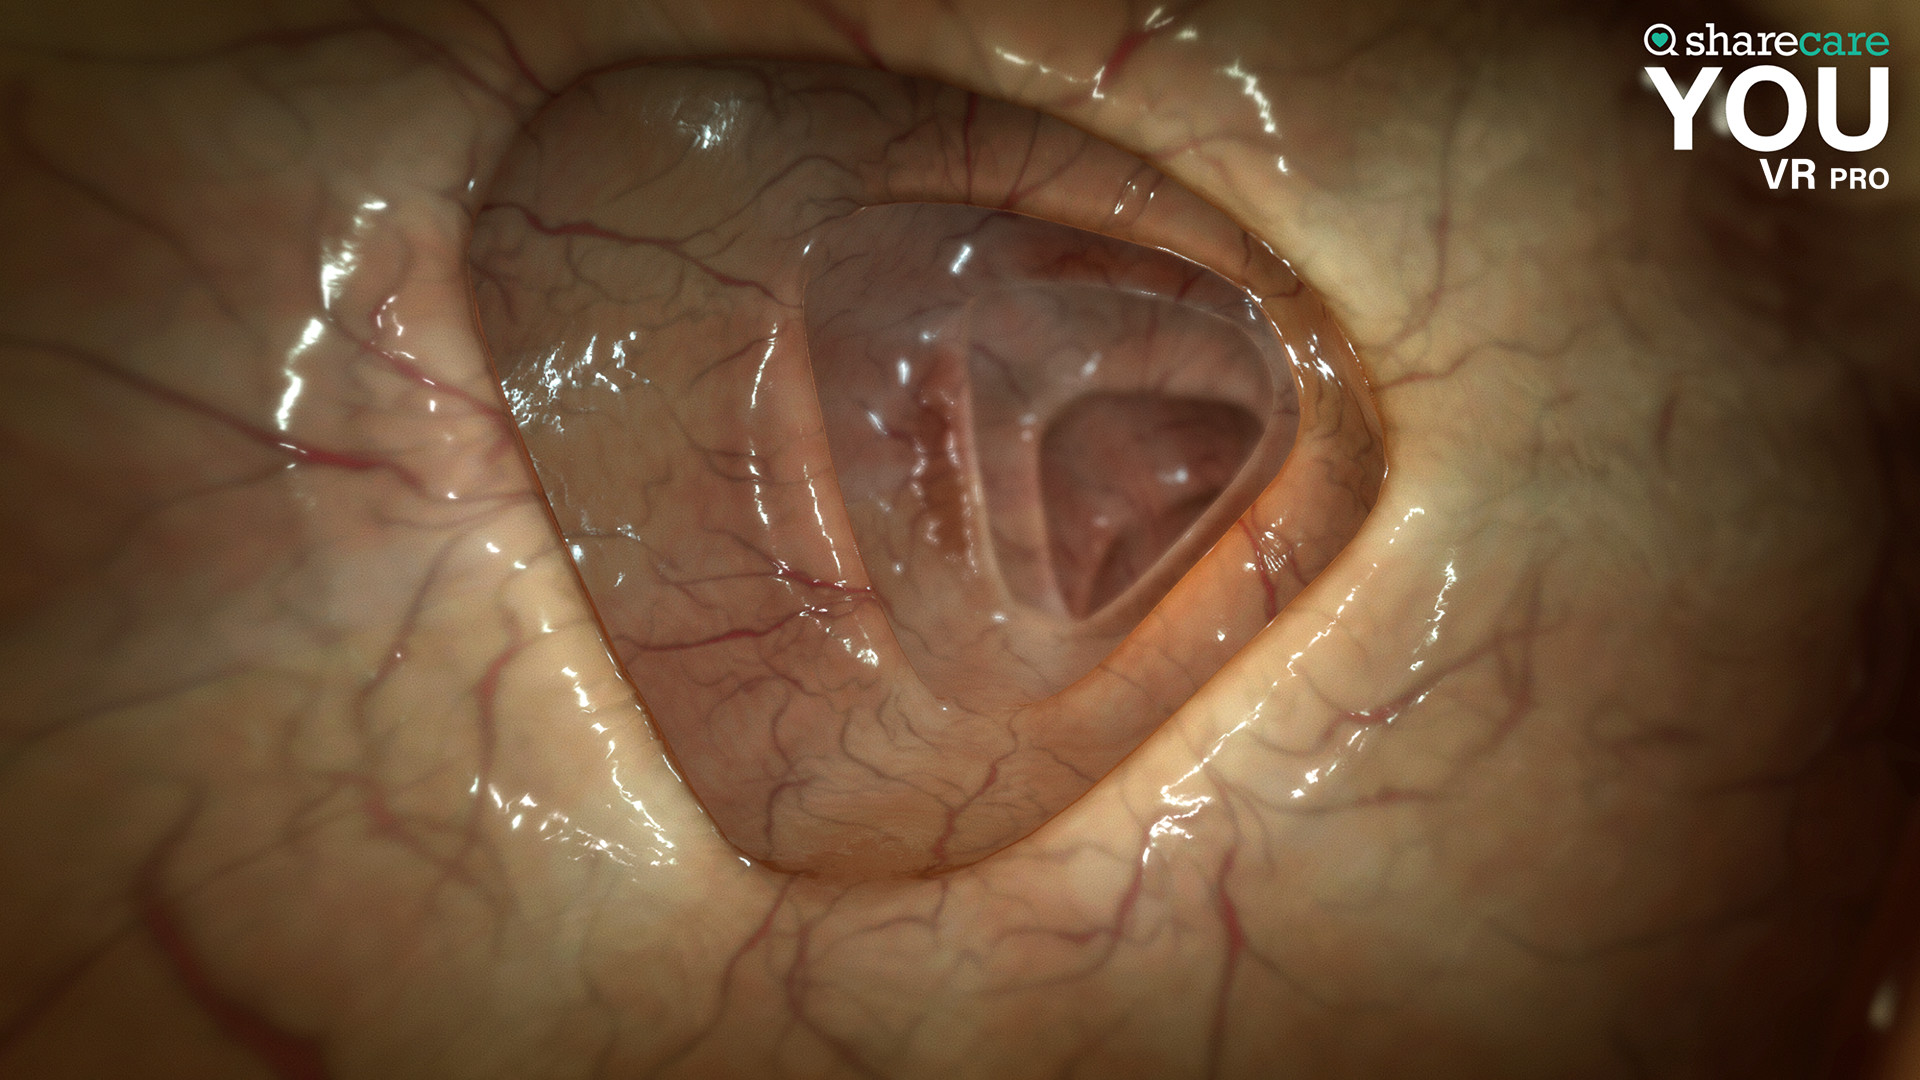

The winner of the 2019 Appy Best VR App is now available on Mac and PC, with more content, bolder graphics, and enhanced features! Sharecare YOU VR is a fully immersive, photorealistic simulation of the human body, enabling anyone to explore its astonishing details in full 360 degrees. Interested in learning about a specific organ? With the click of a button, travel inside, visualize its natural function, and dive deeper. Want to learn even more? Check out the many tags and labels along the way to gain even more information and insight. Easily customize YOU to better understand physiology and simulate disease. You can even personalize our avatars to be a virtual you – your health, your conditions. It really is all about YOU. With YOU VR PRO, users can create visually compelling, high-quality educational content. Build YOU lectures and presentations easily, with the help of video and voiceover recording, and the ability to draw and add your own text. You can also be the star within these videos using our web-cam feature.

- YOU content - an expanding library of over 40 different scenes to explore including anatomy, physiology, conditions, and treatments